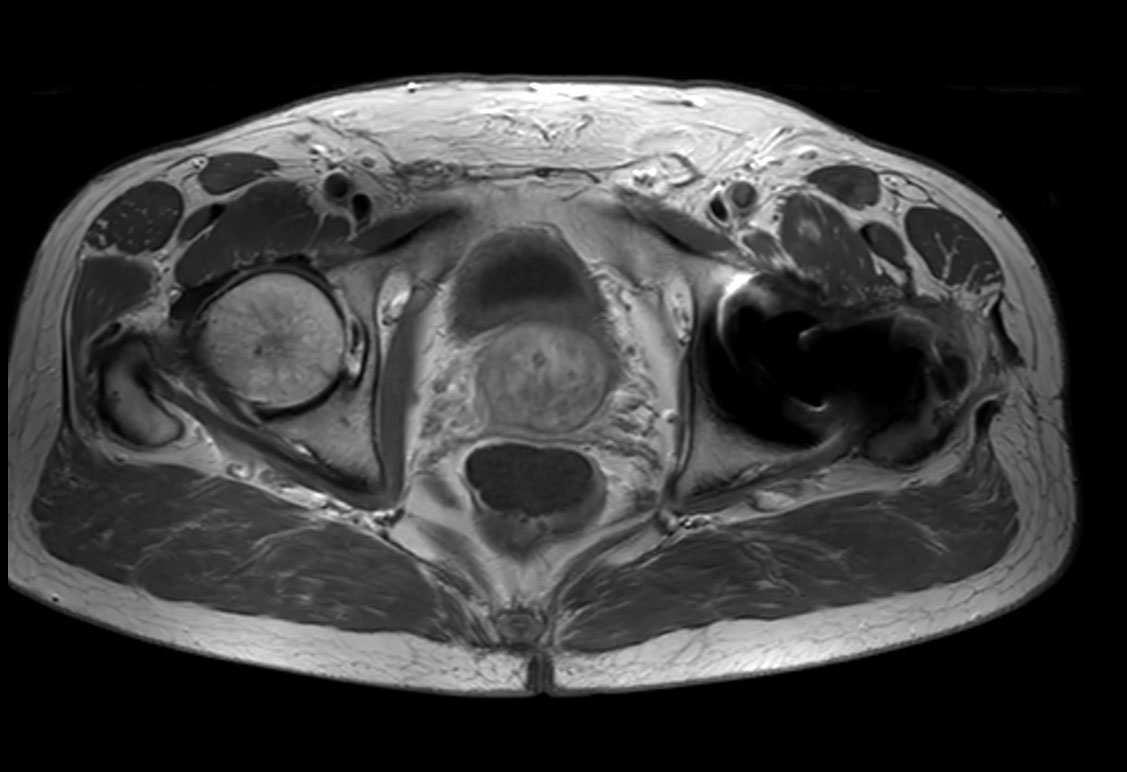

Axial T2w TSE